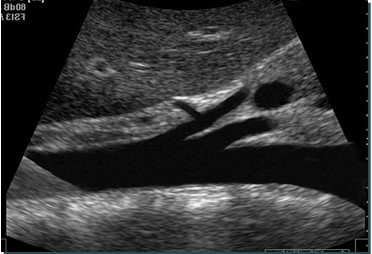

<p>What is this structure?</p>

What is this structure?

Aorta with the SMA coming off the top